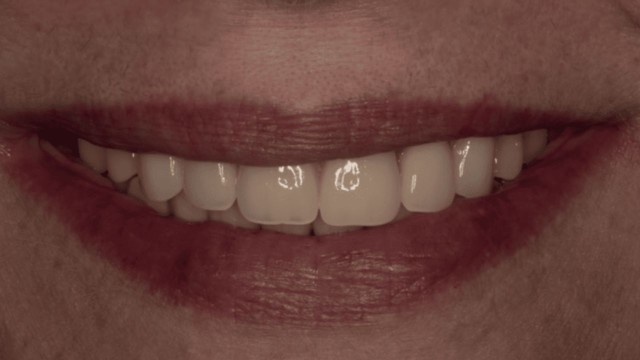

Sorriso della paziente con le protesi provvisorie. E’ stato possibile un ottimo recupero estetico e funzionale grazie anche all’aumento della dimensione verticale che ha riportato ad una corretta relazione tra le due arcate.